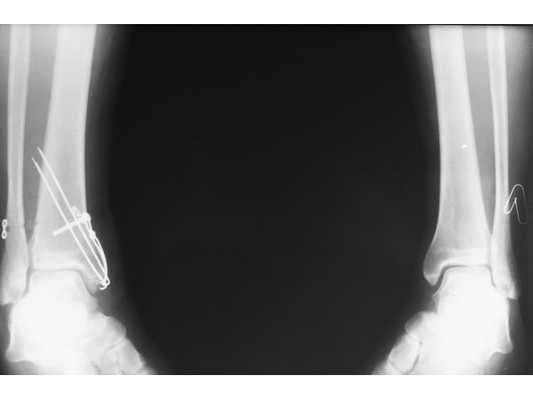

После обследования и уменьшения отёка мягких тканей на четвёртые сутки с момента травмы больному проведено оперативное вмешательство. Под спинномозговой анестезией выполнена открытая репозиция перелома внутренней лодыжки правой голени спицами и стягивающей проволочной петлёй, фиксация дистального межберцового синдесмоза стягивающей петлёй с упорными металлическими площадками.

Ранний послеоперационный период протекал без осложнений. На третьи сутки после операции конечность фиксирована гипсовой повязкой от нижней трети правого бедра до плюснефаланговых суставов. Пациент активизирован с опорой на костыли без нагрузки на правую нижнюю конечность. Выписан на амбулаторное долечивание под наблюдение районного травмпункта.